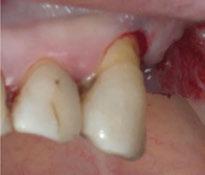

Para ilustrar el proceso, presentamos el caso de una mujer joven diagnosticada de carcinoma adenoide quístico en la región posterior del hemipaladar izquierdo (Figuras 1 y 2). El procedimiento quirúrgico realizado fue una

maxilectomía parcial que incluyó las piezas 24-26 y desde el reborde alveolar hasta la base del cráneo (Figuras 3 y 4). En este caso, la órbita y el globo ocular pudieron ser preservados. La reconstrucción inmediata se realizó mediante un colgajo de músculo temporal homolateral (Figura 5) y el defecto de la fosa temporal fue cubierto mediante una malla de titanio. Posteriormente, la paciente recibió radioterapia (Figuras 6 y 7). 2 años más tarde se diseñó un IS con anclaje en el arbotante nasomaxilar, zona subnasal izquierda

Figura 3. Maxilectomía parcial.

Figura 4. Defecto maxilar tras resección del tumor.